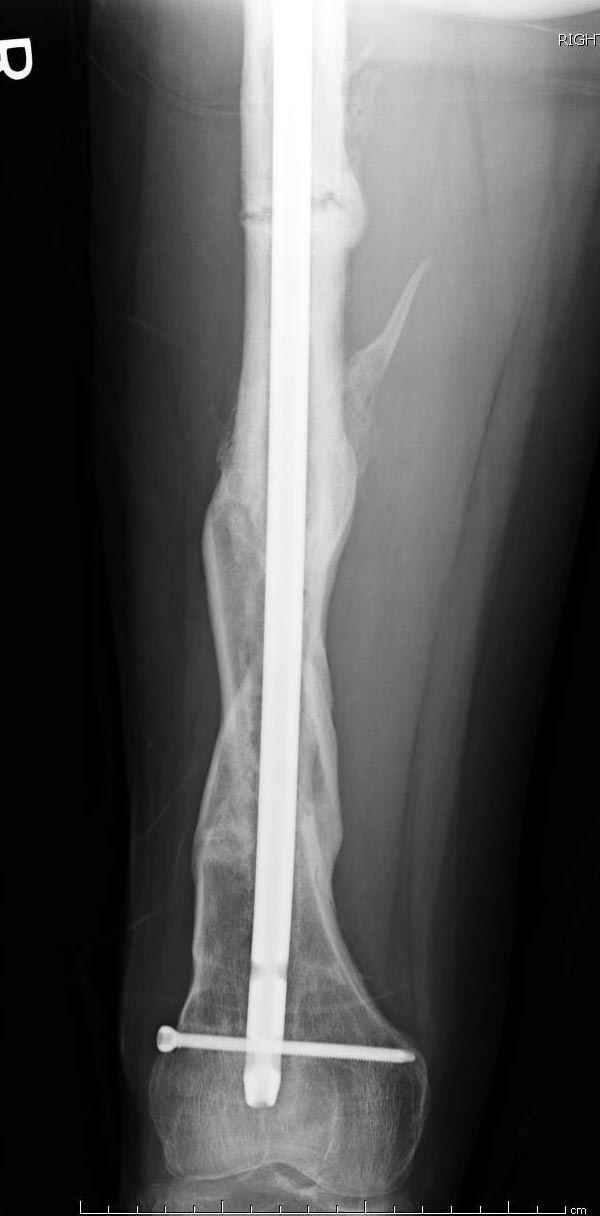

Рутинный интрамедуллярный остеосинтез с расверливанием и с фиксацией реконструктивным трокантерик штифтом (рис №1, №2),

если первые 4 месяца послеоперационного периода проходил без проблем, но на 5 месяце появились боли в дистальном отделе бедра и температура, т.е. симптомы медуллярного инфицирования (рис №3, №4).

Замена реконструктивного штифта “Custom made Nail” с антибиотиком (рис №5, №6),

после промывки канала с рассверливанием внутреннего кортекса, через 4 недели антибиотический штифт удалили, оспалителный процесс остановлен и бедро сросся.

Мы не дождались “Happy End”, у больного IQ в пределах 70%, через 6 месяцев вернулся после небольшой травмы, споткнувшись получил перелом

того же бедра (рис №7).

На следующий день произвели интрамедуллярный остеосинтез: этапы во время операции (рис №8, №9)

и последующих снимках (рис №10, 11, 12, 13) перелом сростается и передвигается с полной нагрузкой.

При обзоре причин перелома, на снимке №2 обнаружили, что один из стержней аппарата наружной фиксации проходил только через передний кортекальный слой, что создало стрессовую зону на бедре и в результате перелом из-за незначительной травмы.